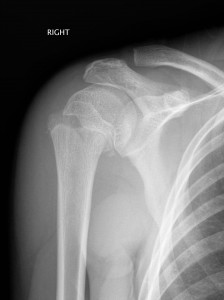

- Adolescents are more likely to have Salter-Harris fractures around the physis.

Above: Proximal humerus fracture with 40 degrees of angulation

Above: Salter-Harris II fracture of proximal humerus